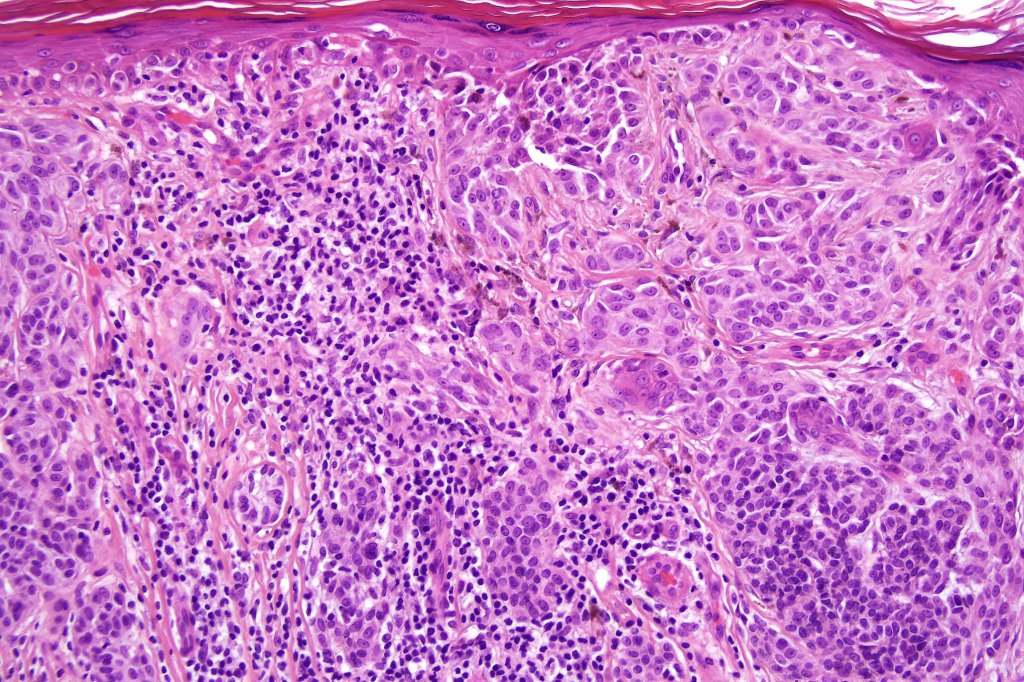

Combined congenital & blue nevus (same case as the clinical photographs coursty of Dr. Antonina Kalmykova